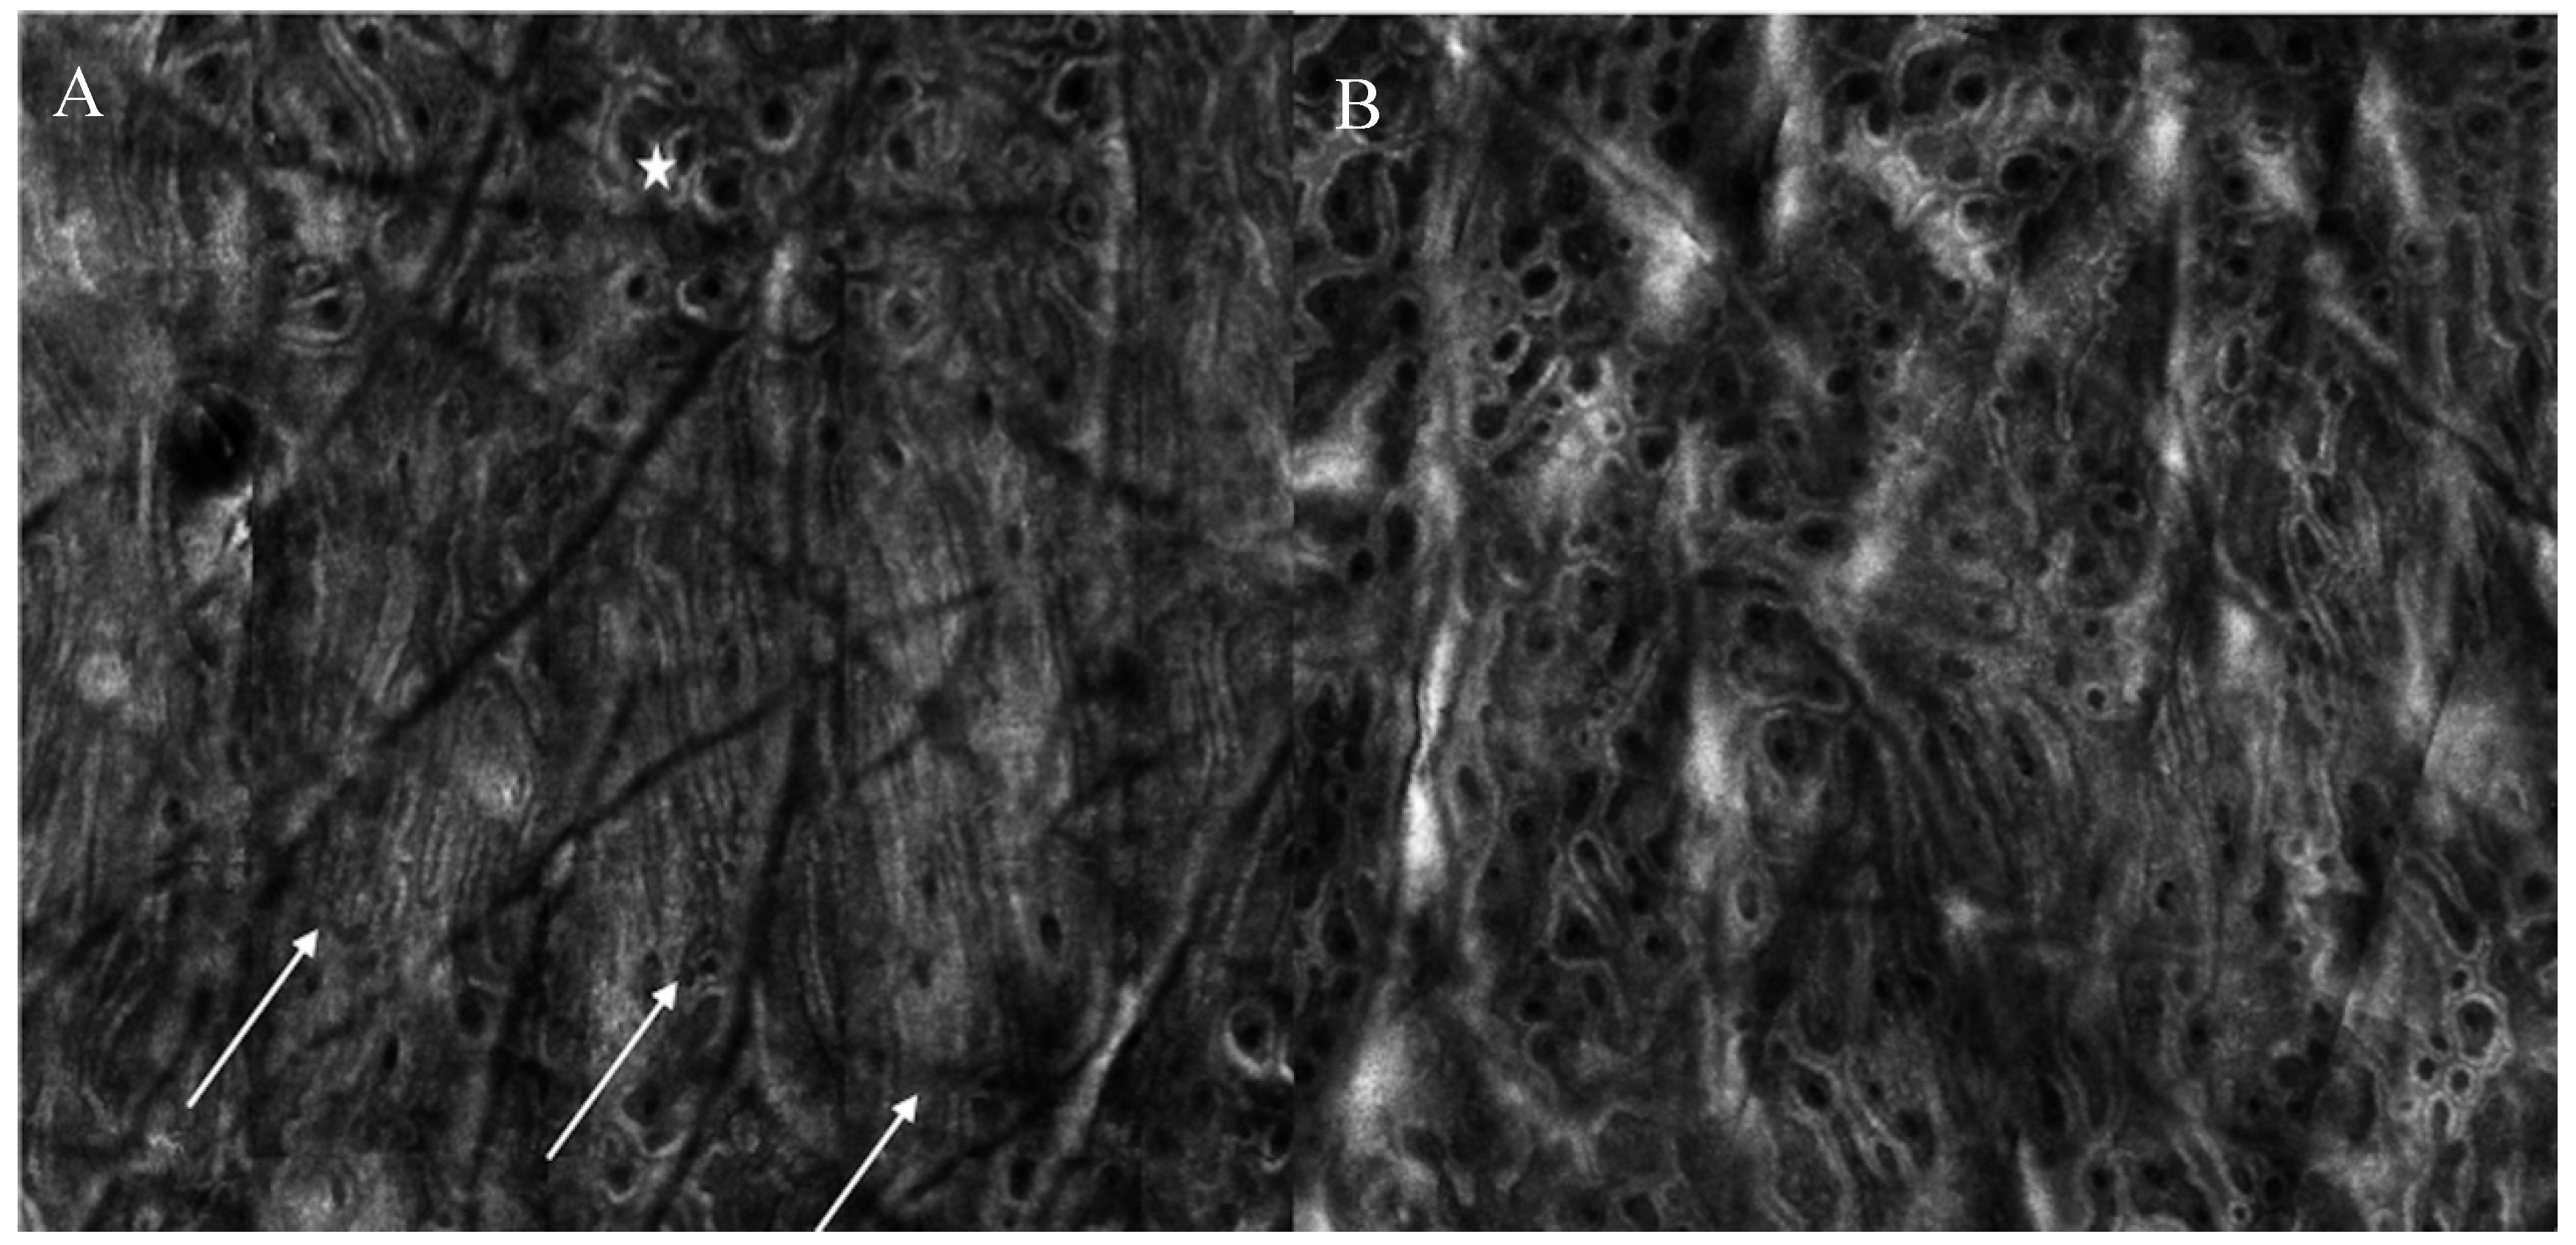

Differently from what observed for dark circles, melasma patients can show pigmentation located at different layers. Jo et al. compared the effects of PSL and Q-switched laser on melasma. After treatment, either an increase of activated melanocytes at basal layer of epidermis or an increased amount of melanophages were observed at upper dermis 24 h after treatment [27]. Interestingly, the presence of dendritic-shaped cells after treatment has been associated with a relapse of melasma 3 months after multiple sessions of Q-switched laser treatment [28]. Figure 3 shows the presence of superficial pigmentation represented by mottled pigmentation at epidermal level at baseline and the disappearance of the pigmentation after Q-switched laser treatment.

Figure 3. Reflectance confocal microscopy images of patient showing superficial melasma at baseline and 3 months after Q-switched laser treatment. (A) At baseline, mottled pigmentation (white arrow) can be observed at epidermal level (B) After treatment, RCM shows disappearance of mottled pigmentation and recover of regular honeycombed pattern.